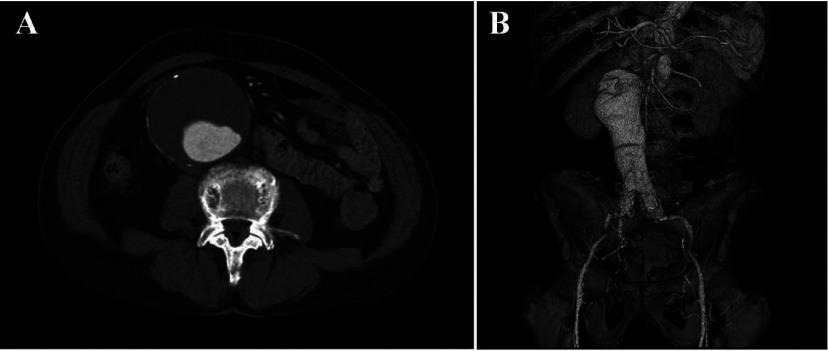

Computed tomography (CT) revealed a massive infrarenal AAA that measured 81 mm in maximum diameter (Fig. 2A). 3-dimensional computed tomography (3D-CT) showed the fusiform AAA with severe angulated proximal neck (Fig. 2B). We diagnosed the disease as advanced gastric cancer concomitant with AAA. Then he was referred to our institution for the operation of both lesions.

Fig. 2.

A: Contrast-enhanced computed tomography (CT) revealed a huge infrarenal abdominal aortic aneurysm (AAA) that measured 81 mm in maximum diameter.

B: 3-dimensional computed tomography (3D-CT) showed the fusiform AAA with a severe angulated proximal neck.